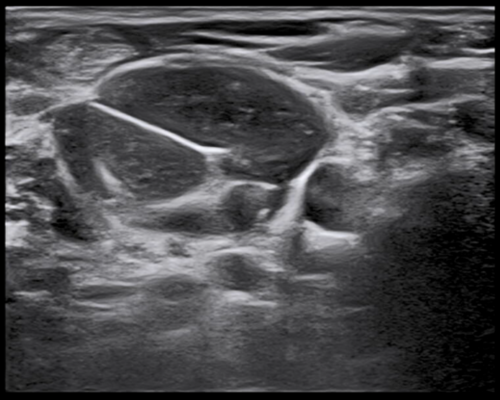

Needle Enhancement improves the visibility of the needle position during biopsy procedure for enhanced operation precision.